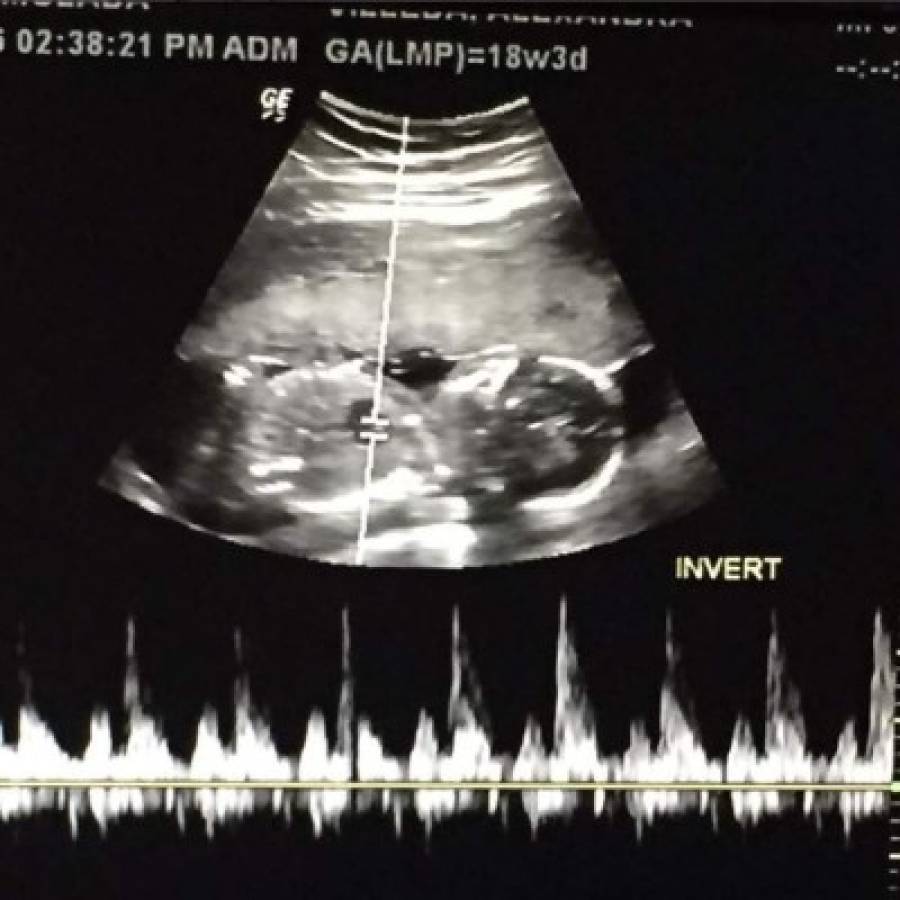

“Mi Principe. Muero por tenerte entre mis brazos y nunca soltarte!! #18semanas y #3dias”, escribió la artista acompañándolo con la imagen de su ultrasonido.